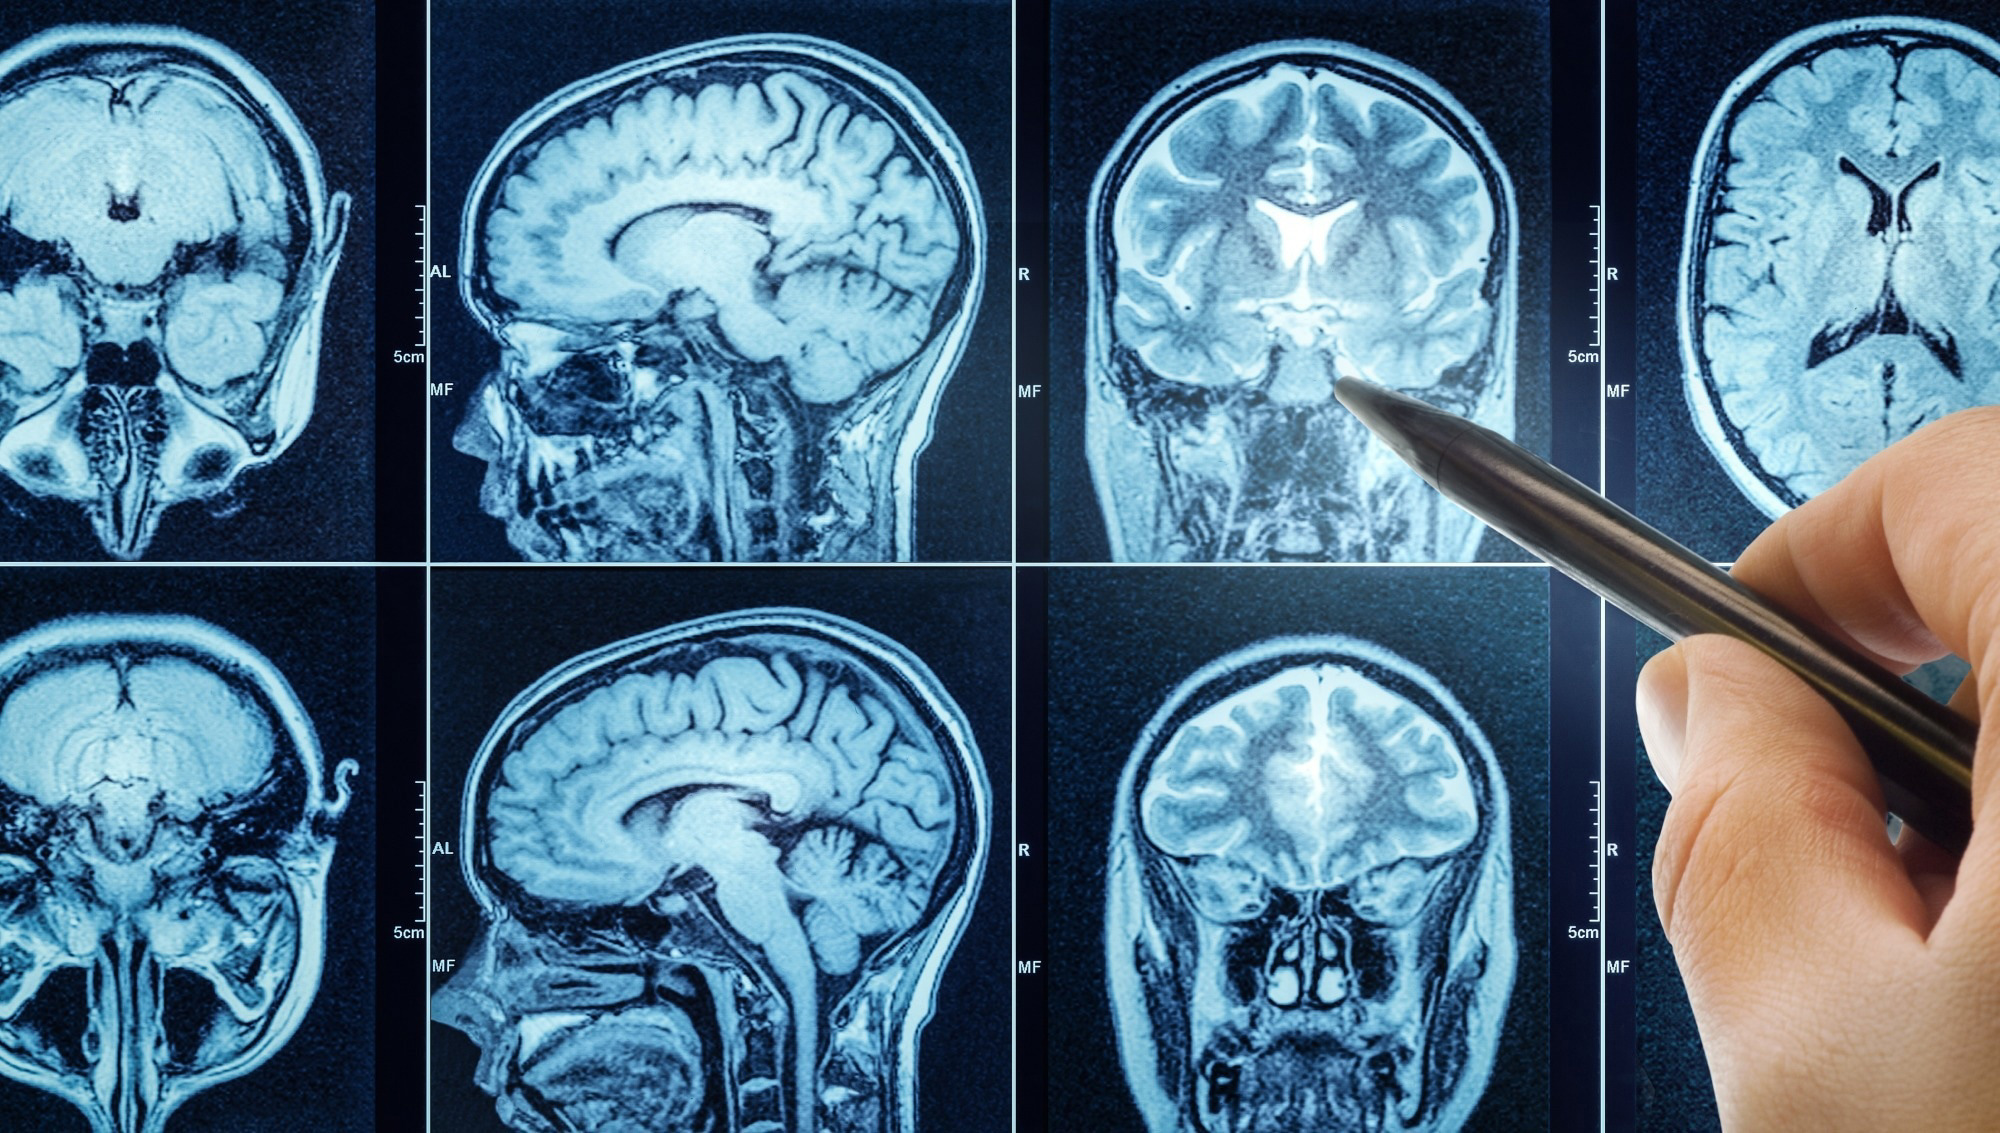

This study evaluated the microscopic safety of ultrasound neuromodulation delivered using the BrainSonix BX Pulsar 1002 by performing histological analysis of human brain tissue following exposure. Rather than relying solely on clinical outcomes or imaging, the authors examined tissue at the cellular level to detect subtle structural, vascular, or inflammatory changes.

Under the tested conditions, no evidence of ultrasound-induced tissue injury was observed, including no hemorrhage, necrosis, or inflammatory response. This work provided a critical layer of biological validation, strengthening confidence in the tissue-level safety of low-intensity focused ultrasound. These results were consistent even at intensities as high as ISPTA.3= 14 W/cm2. The findings supported the use of the BX Pulsar 1002 in protocols involving repeated exposures and deep-brain targets, complementing other safety evidence across the neuromodulation literature.